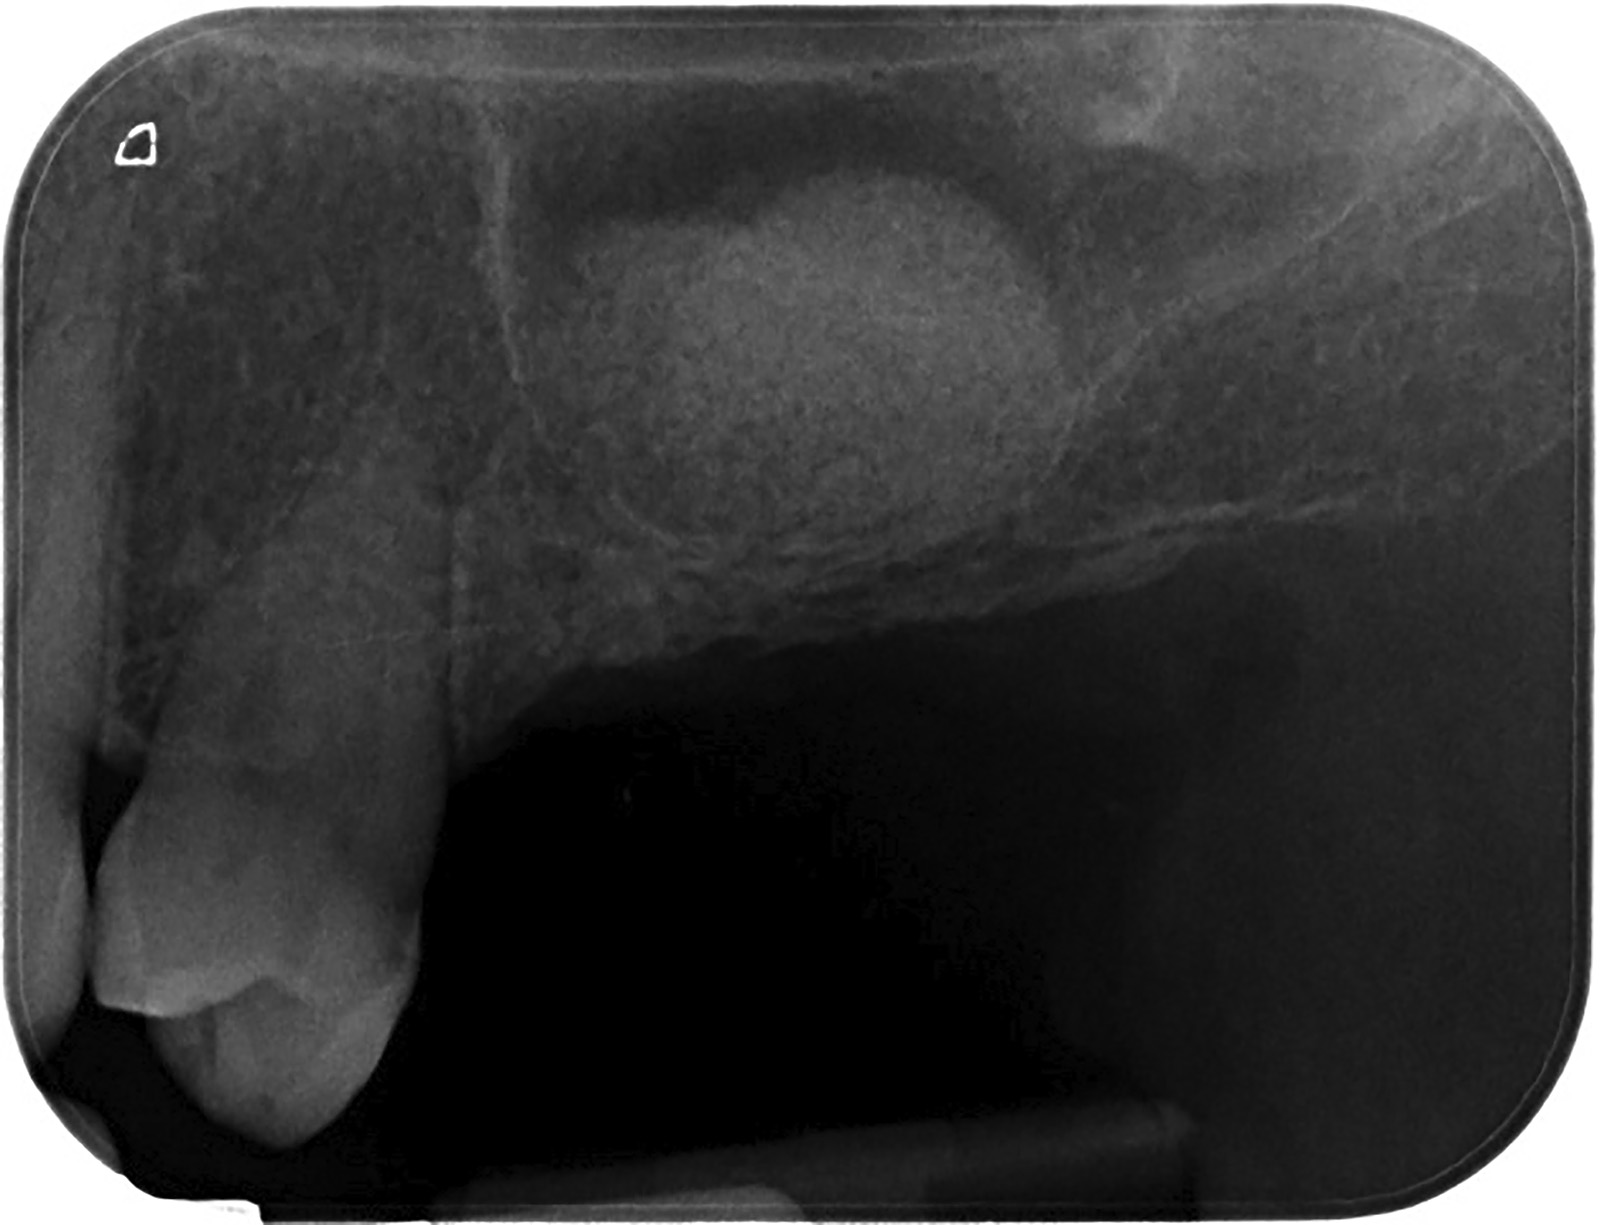

PREMESSA: in seguito all’estrazione dell’incisivo laterale superiore di destra, resasi necessaria per cause batteriche, si decide di affrontare il caso con il posizionamento di un impianto in sostituzione dell’elemento mancante dopo guarigione del sito infetto. Con tecniche rigenerative sia dei tessuti ossei mancanti a causa dell’infezione pregressa, sia dei tessuti gengivali che appaiono inizialmente troppo spostati in alto, si ripristina una corretta morfologia delle parabole (contorni) gengivali e delle papille interdentali (triangoli di gengiva tra due denti vicini).

Vengono utilizzati 2 tipi di provvisori: il primo, cementato ai denti vicini, viene utilizzato dal momento dell’estrazione del dente fino ad impianto osteointegrato (circa 6 mesi); il secondo, avvitato direttamente all’impianto, ha una funzione di prova estetica ma soprattutto di guida per la maturazione dei tessuti gengivali peri-implantari portandoli verso la maturazione completa prima di posizionare la corona finale in disilicato di litio.